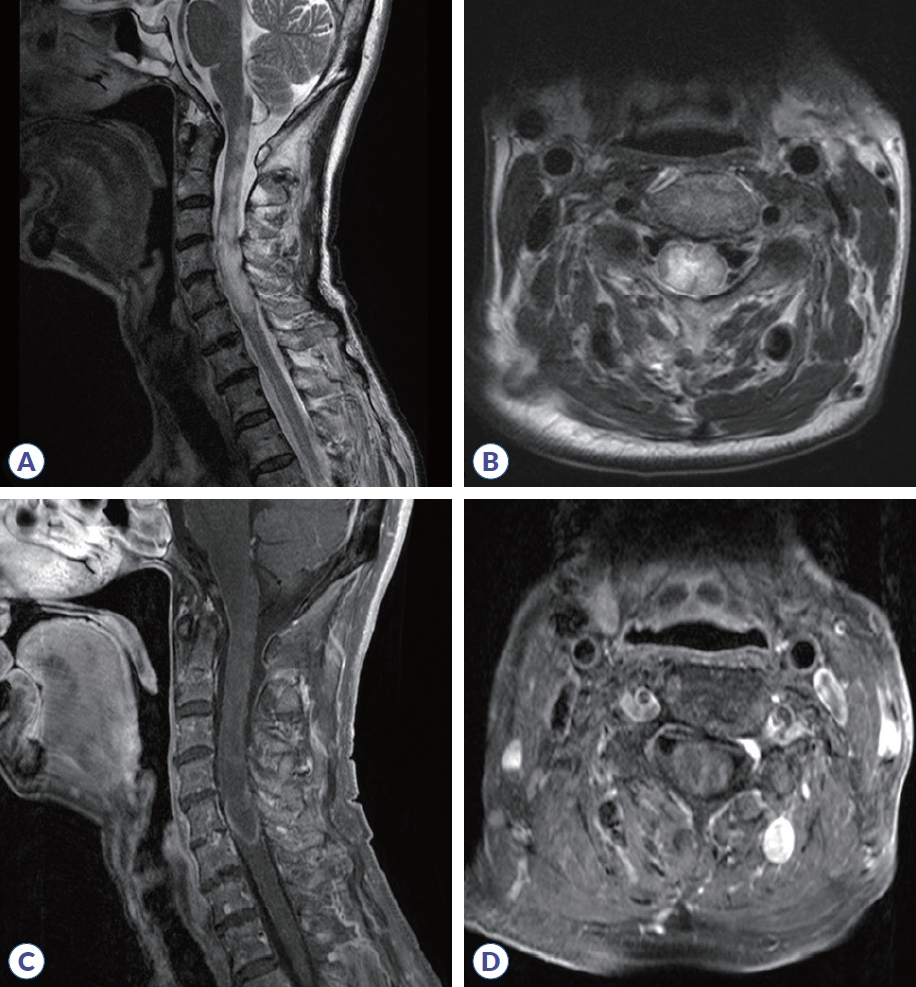

A Case Report of MOG Antibody-Associated Disease (MOGAD) with Isolated Brainstem and Spinal Cord Involvement   (26 times)

Ye Lin Kim, Juhee Chae, Sun-Young Oh

J Mult Scler Neuroimmunol. 2024;15(2):81-84.   Published online December 31, 2024